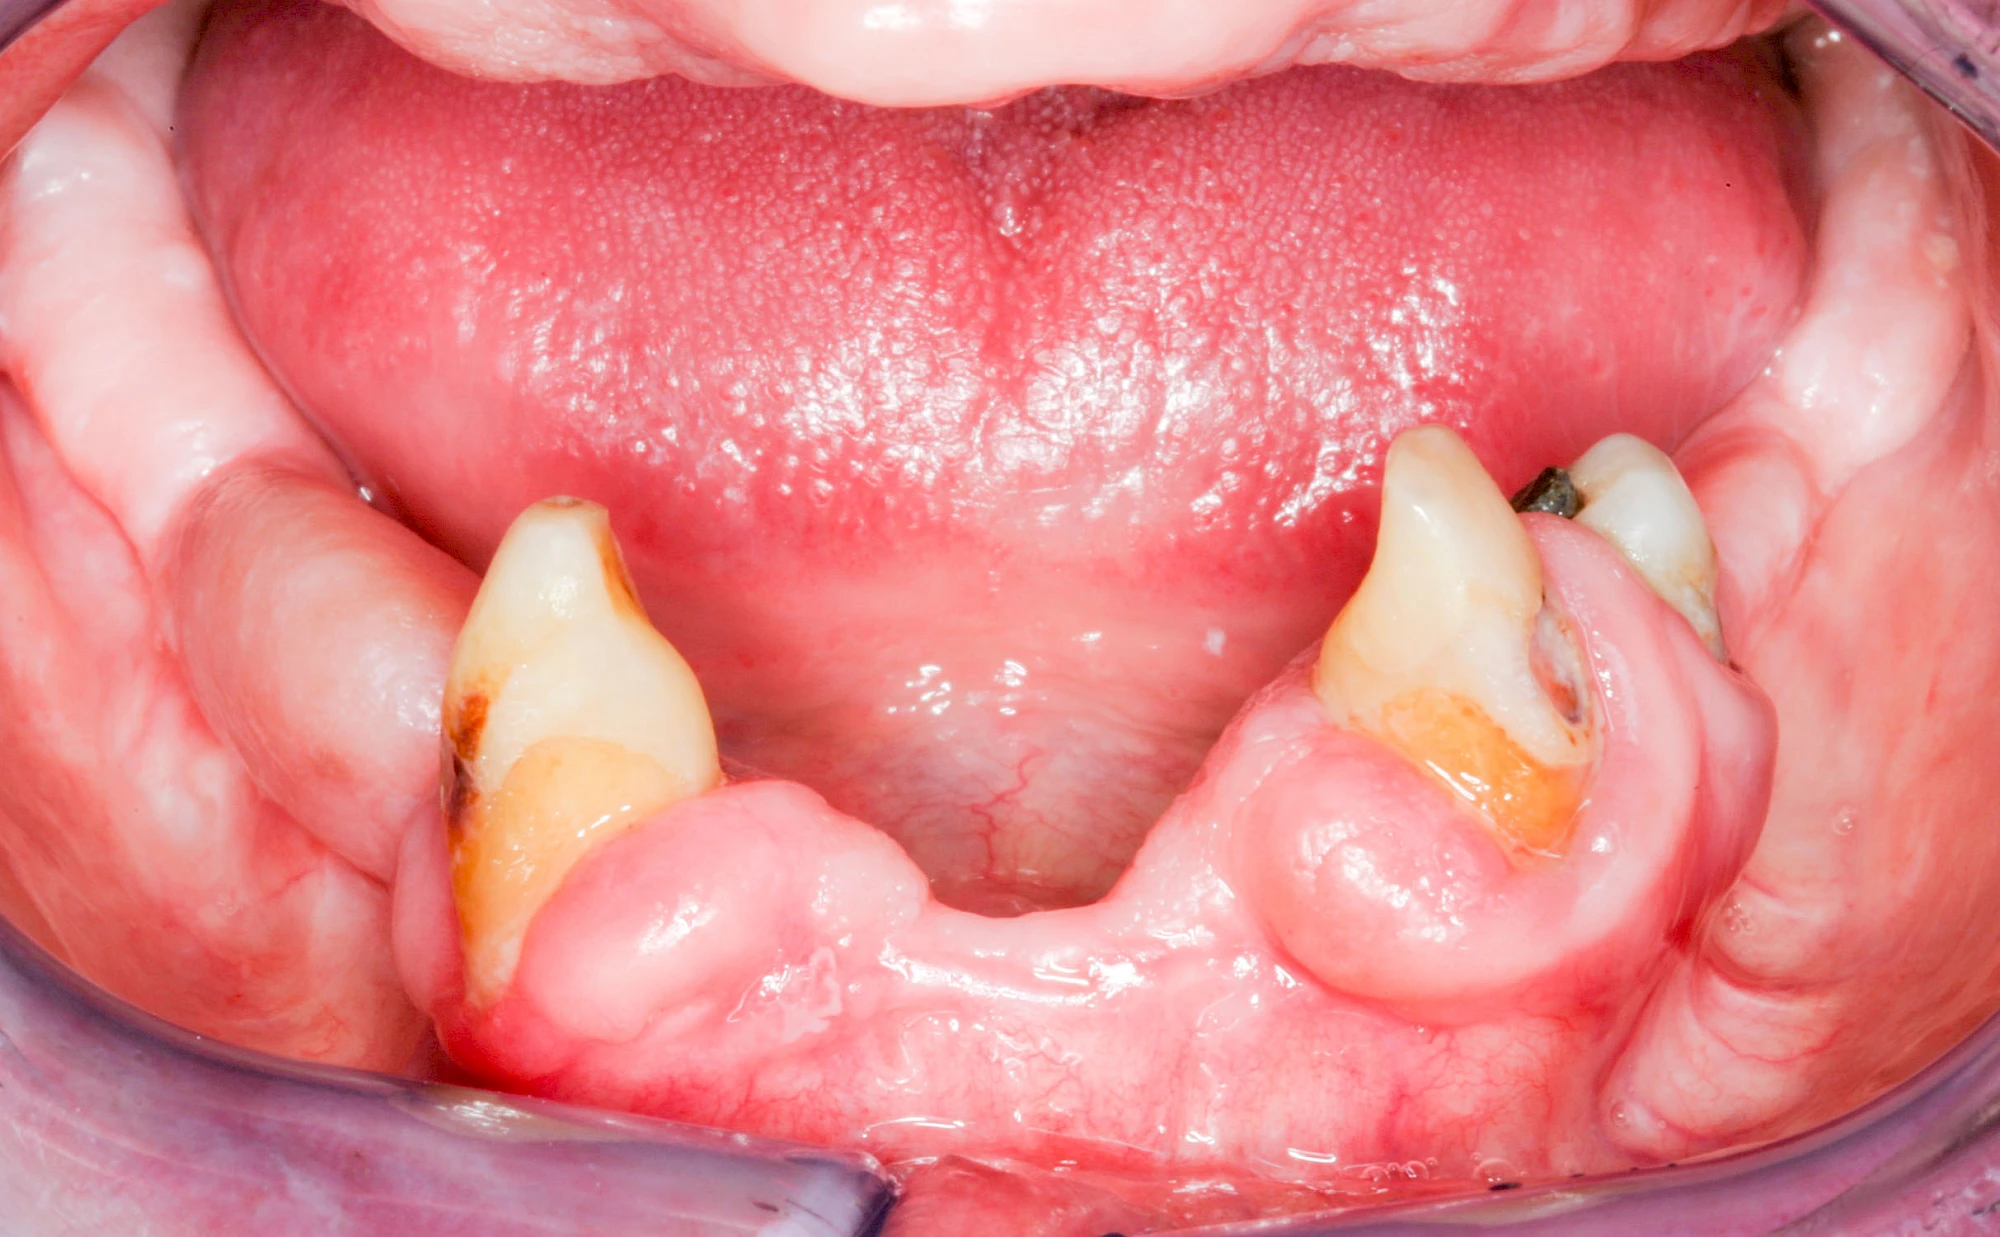

Gingivitis & Parodontitis: Stadien

Ist zunächst nur das Zahnfleisch von der Entzündung betroffen, spricht man von Gingivitis. Später, wenn auch der Knochen um die Zähne herum entzündet ist, spricht man von einer Parodontitis. Bei der Parodontitis wird der Knochen nach und nach abgebaut und das Zahnfleisch zieht sich zurück. Die Zahnhälse und Zahnwurzeloberflächen liegen mehr und mehr frei. Die Zähne werden zunehmend lockerer und fallen schließlich aus.

Bakterien in den Zahnbelägen greifen neben den Zähnen auch das Zahnfleisch (Gingiva) und den gesamten Zahnhalteapparat (Parodont) an. Der Körper reagiert mit einer Entzündung, sichtbar als Rötung und Schwellung. Meist blutet das Zahnfleisch z .B. beim Essen oder auch beim Putzen der Zähne.